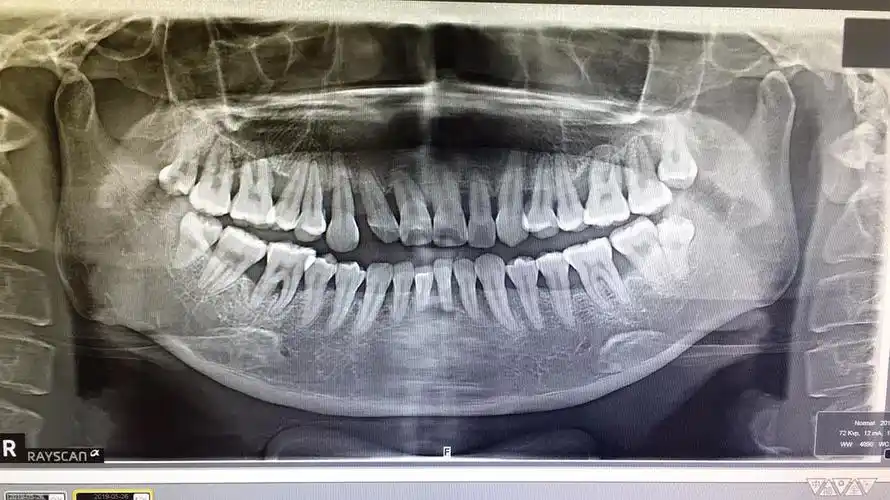

牙槽骨吸收不是牙周炎造成的